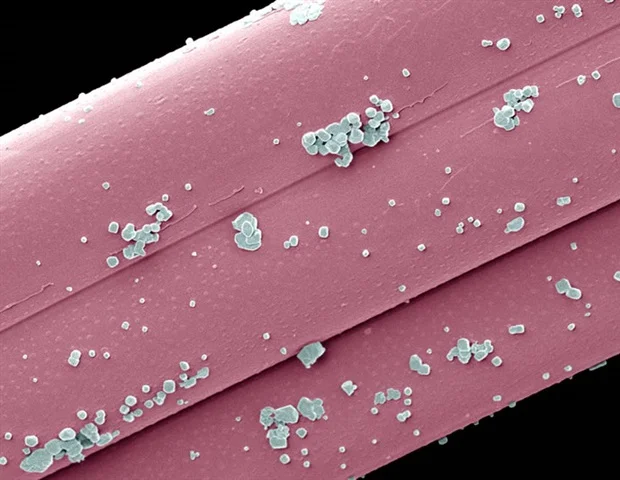

מהנדסים מאוניברסיטת פנסילבניה פיתחו סוג חדש של ננו-חלקיקי שומנים (LNP) שיוכל לשמש יום אחד כאימונותרפיה אוניברסלית לסרטן היוצרים גידולים מוצקים,

מהנדסים מאוניברסיטת פנסילבניה פיתחו סוג חדש של ננו-חלקיקי שומנים (LNP) שיוכל לשמש יום אחד כאימונותרפיה אוניברסלית לסרטן היוצרים גידולים מוצקים,